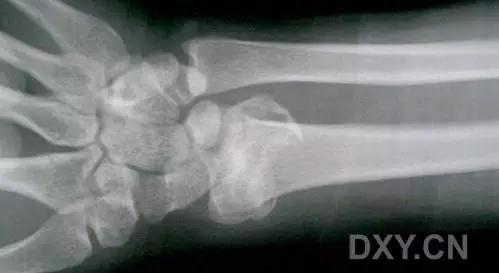

9. Essex-Lopresti 骨折

是桡骨头骨折伴有下尺桡关节脱位,导致骨间膜损伤,桡骨短缩。此种损伤,桡骨头骨折的诊断往往是明确的,容易忽视的是下尺桡关节脱位,特别是早期,下尺桡关节的症状不明显,X 线表示也不明显。

Essex-Lopresti 损伤。前后位(A)和侧位(B)示桡骨头关节内骨折(白色实线箭头);(C~E)伤后 1 个月复诊,患者诉腕关节疼痛,X 线(C,D)发现下尺桡关节脱位,(E)CT 进一步证实损伤的存在 (来源:Radiol Clin North Am. 2015 Jul;53(4):717-36)